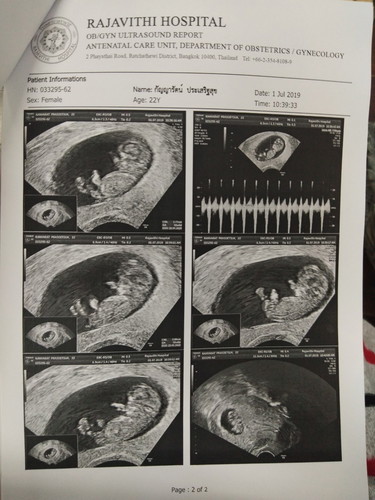

เมื่อวานมีเลือดออกค่ะ วันนี้ไปตรวจ คุณหมอบอกว่าแท้งคุกคาม อัลตราซาวด์ดูน้องยังแข็งแรง สมบูรณ์ดีค่ะ ฉีดยากันแท้ง 1 เข็ม งดกิจกรรม หมอสั่งให้นอน กิน อาบน้ำ ทำแค่นี้ เป็นเวลา 1 อาทิตย์ ? ห้ามดูหนังเครียดๆ กินไข่ขาวเยอะๆ ดื่มน้ำเยอะๆ นอนพักผ่อนให้มาก ด้วยความที่เป็นคนทำงานไม่อยู่สุข มาวันนี้แม่ต้องอยู่เฉย+กินๆๆเพื่อหนูเลยรู้ไหม รักหนูนะคะ #ท้องแรก ?